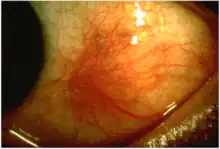

Scleritis is a serious inflammatory disease that affects the white outer coating of the eye, known as the sclera. The disease is often contracted through association with other diseases of the body, such as granulomatosis with polyangiitis or rheumatoid arthritis. There are three types of scleritis: diffuse scleritis (the most common), nodular scleritis, and necrotizing scleritis (the most severe). Scleritis may be the first symptom of onset of connective tissue disease.[1]

- Redness of the sclera and conjunctiva, sometimes changing to a purple hue

The pain of episcleritis is less severe than in scleritis.[4] In hyperemia, there is a visible increase in the blood flow to the sclera (hyperaemia), which accounts for the redness of the eye. Unlike in conjunctivitis, this redness will not move with gentle pressure to the conjunctiva.

Scleritis is best detected by examining the sclera in daylight; retracting the lids helps determine the extent of involvement. Other aspects of the eye exam (i.e. visual acuity testing, slit lamp examination, etc.) may be normal. Scleritis may be differentiated from episcleritis by using phenylephrine eye drops, which causes blanching of the blood vessels in episcleritis, but not in scleritis.[4]